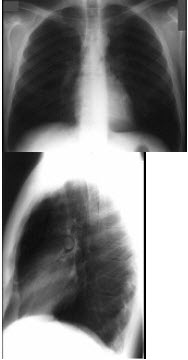

男性,62岁,常感胸闷、气逼,X线检查如图,最可能的诊断是()

A.右侧肺大疱

B.右侧气胸

C.右侧肺脓肿

D.右侧胸膜肥厚

E.右肺炎